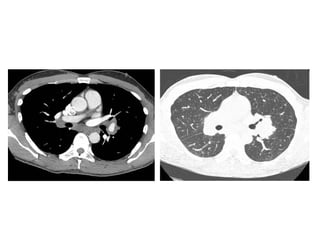

Exudative phase of AIP in a 22-year-old man, high-resolution CT image

shows bilateral ground-glass opacities (arrowheads) and

consolidation (arrow) in the dependent areas of the lungs, the

anterior zones of the lungs are relatively spared

Fibrotic phase of AIP in a 53-year-old woman who survived the acute

phase of the disease, CT image shows fibrotic changes with traction

bronchiectasis and architectural distortion predominantly in the

nondependent areas of the lungs (arrow), a coexisting right pleural

effusion is seen (arrowhead)